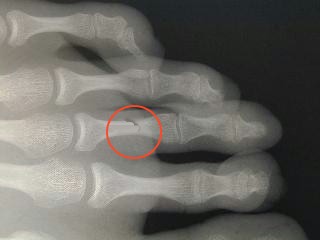

4 - atteinte des os : Que nous montre cette radiographie ?

radiographie collège Jules Renard 53000 Laval

Une déchirure musculaire Une fracture Une entorse